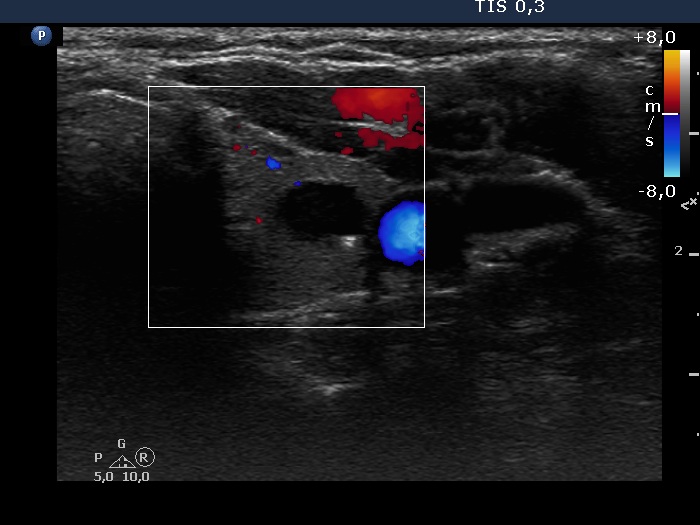

Consecutive patients with the final diagnosis of Hashimoto's thyroiditis - case 1 (1789) (ultrasonographic picture 5)

Left lobe, transverse scan, color Doppler mode. The vascularization is non-specific.